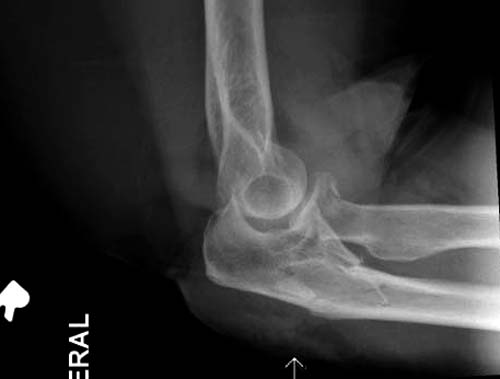

можно увидеть на обычных рентген снимках. Негативный рентген при

исследовании локтевого сустава не означает отсутствие перелома. Если

имеется“fat pad sign”, характерный симптом для внутрисуставных

повреждений, тогда можно ставить диагноз перелом головки луча! Гематома

внутрисуставного перелома смещает жировое тело и на боковом снимке

проявляется в виде“паруса”.

Chapman S (1991). "The sail sign". Br J Hosp Med 46 (6): 399–400.